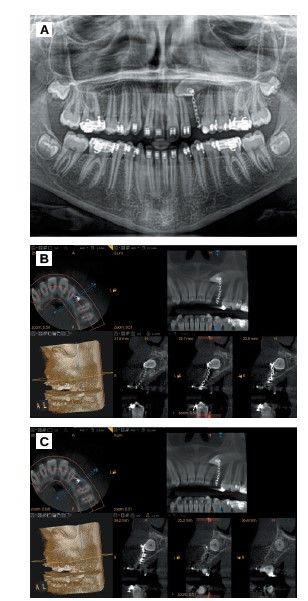

A conical beam computed tomography (CBCT) scan is performed to evaluate the exact position of the impacted canine which is located in mixed position, with the root completely formed in Nolla6 stage 10 and Moorrees stage 67, in contact with the cortical of the sinus and the crown with the cusp breaking the vestibular cortical. Around the crown a radiolucency is observed that corresponds to the pericoronary sac.

Measurements were made with the CBCT to determine the exact dimensions of the canine and the receiving area to ensure that the space was correct and was not necessary to modify it with orthodontics. In addition, anatomical relationships with adjacent structures were evaluated to avoid possible complications during surgery (Figure 1).